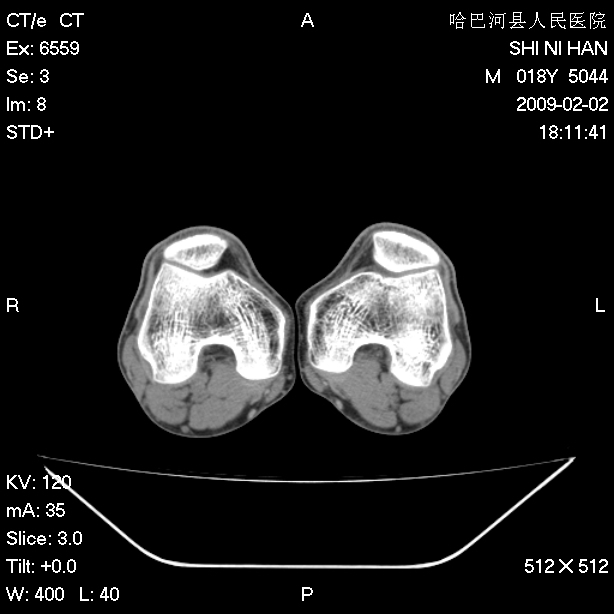

标题: CT17889:外伤后右膝关节反复疼痛3年余 [打印本页]

标题: CT17889:外伤后右膝关节反复疼痛3年余

ct未见明显异常。关节腔未见明显积液,半月板未见明显撕裂。但最好还是mri看看韧带及半月板情况。